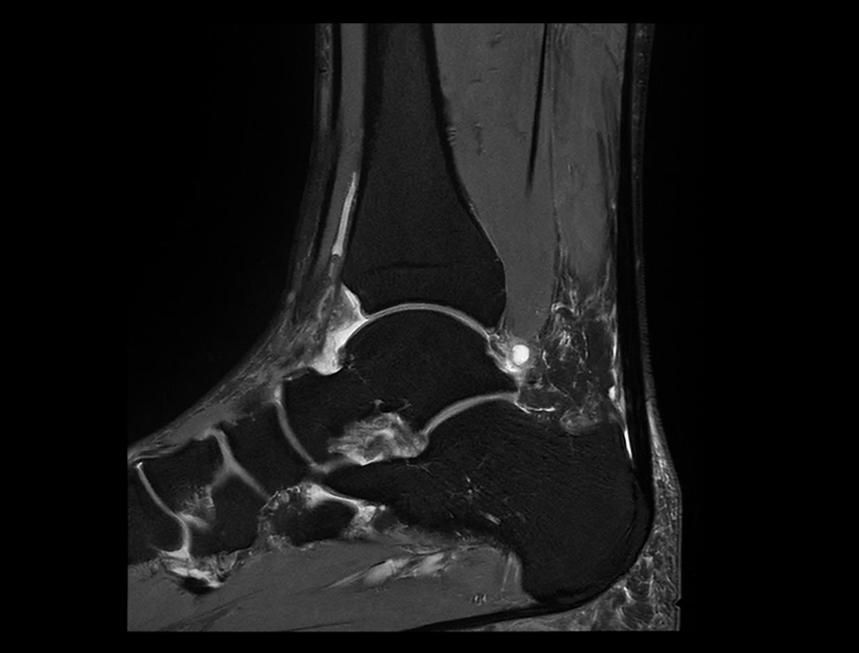

踝关节 PDW FS